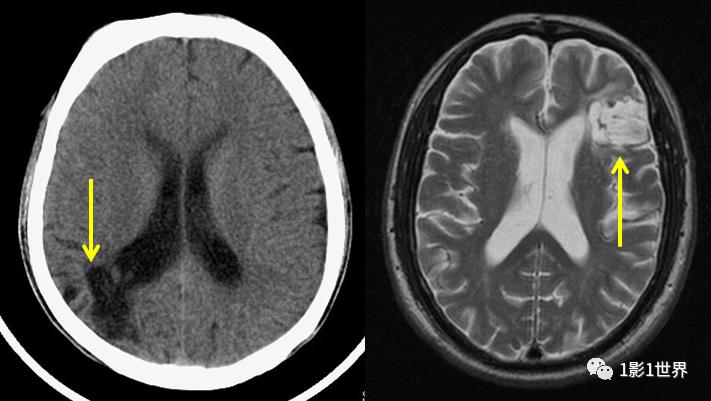

| CT影像表现 | 超急性期/急性期: • 早期征象:脑沟、脑池变浅或消失,脑白质密度轻度减低(“致密动脉征”不常见)。 • 典型表现:发病24小时后,可见片状、楔形的低密度灶,边界模糊,范围与供血动脉区一致。 • 占位效应:早期不明显,随时间推移可出现,表现为脑室受压、中线移位。 • 脑出血转化:部分梗死灶内可继发出血,密度不均匀。 |

慢性期: • 形态:表现为低密度的囊腔,形态不规则,边界清晰锐利。 • 密度:与脑脊液密度相近(CT值接近0-10 HU)。 • 周围:常伴有局限性脑萎缩,如邻近的脑沟增深、脑室扩大。 • 占位效应:**无**或极轻微,甚至因局部萎缩而有“负占位”效应。 |

| MRI影像表现 | 这是诊断急性脑梗最敏感的检查 • 超急性期 (<6小时): • DWI (弥散加权成像):呈明显高信号 (“亮”信号),这是诊断早期脑梗的金标准。 • ADC (表观弥散系数):呈低信号 (“暗”信号),代表细胞毒性水肿。 • FLAIR/T2WI:可能尚未出现异常信号,或仅有轻微改变。 • 急性期 (6小时 - 3天): • DWI/ADC:仍然是高/低信号组合。 • T1WI:呈低信号。 • T2WI/FLAIR:呈高信号。 • GRE/SWI:可早期发现微出血。 • 亚急性/慢性期: • DWI:高信号逐渐减弱,转为等信号。 • T1WI:低信号,可出现“脑膜强化”。 • T2WI/FLAIR:高信号,范围可因水肿消退而相对缩小。 |

MRI表现非常具有特征性 • T1WI:呈极低信号(与脑脊液信号一致)。 • T2WI/FLAIR:呈极高信号(FLAIR上信号很高,与周围脑脊液信号差异大,这是与新鲜梗死的区别)。 • DWI/ADC:呈等信号(因为水分子可以自由弥散,没有受限)。 • GRE/SWI:常可见含铁血黄素沉积导致的低信号环或斑片状低信号(代表陈旧性出血)。 • 周围:可见明显的局部脑萎缩和胶质增生(T2WI/FLAIR上呈高信号的边缘环)。 |